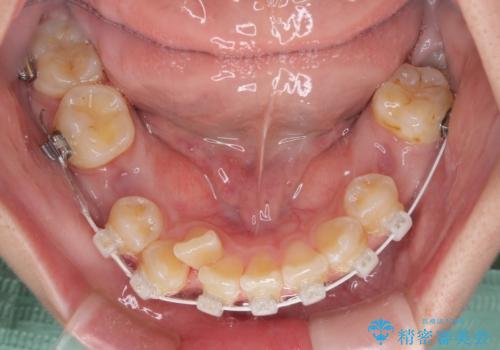

- 八重歯や埋伏している奥歯など、多くの難しい問題を抱えている患者様です。

重度叢生のため、大臼歯をしっかりと咬合させるために、下顎は左右第二小臼歯を、上顎は前歯部の叢生を解消するために左右第一小臼歯を抜歯し、口元の突出感を改善するために、上顎大臼歯が前方に移動しないようにするために、補助装置による架強固定を行うこととしました。

叢生は思ったよりも早期に改善されましたが、舌の突出癖による上下前歯の非接触が全く改善されず、2年間ほど治療期間が延びる結果となってしまいました。